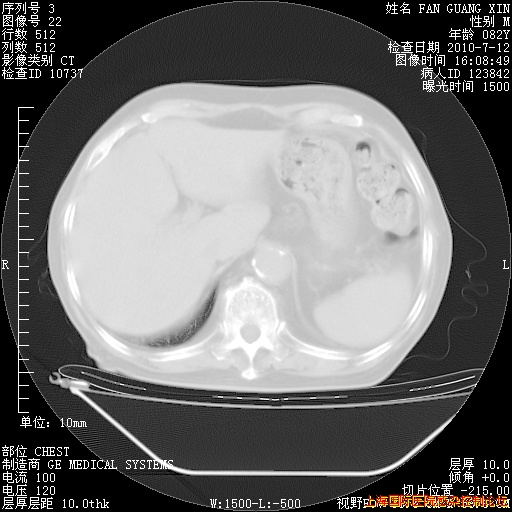

6月12日纵膈窗